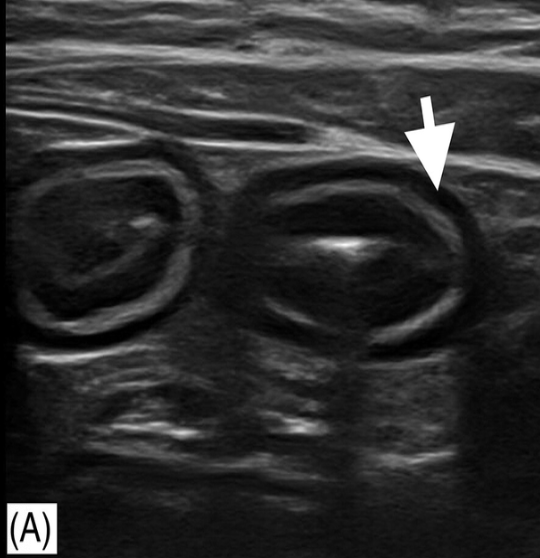

is ultrasound beneficial for diagnosing CIE?

U/S findings are highly variable and no distinguishing features (can use U/S to exclude other causes of chronic GI symptoms)

what are non-specific findings seen on ultrasound in animals with CIE?

thickening of muscularis propria (most common), submucosa, or mucosal layer

abdominal (reactive) lymphadenopathy